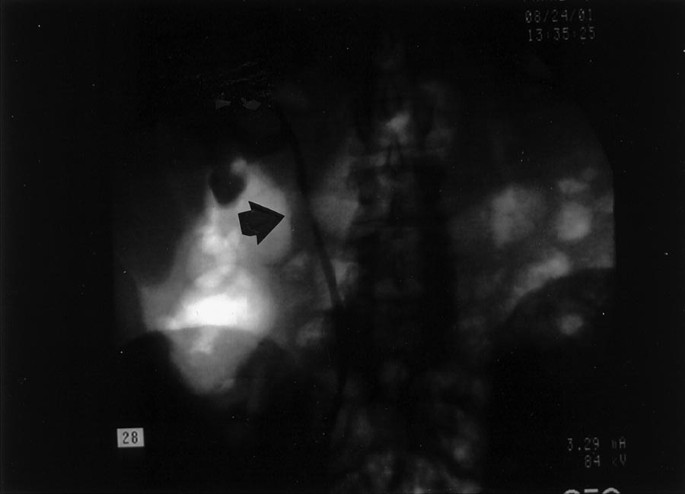

Case 1

A 62-year-old, black, diabetic woman presented with right ureteral stricture caused by complications from a stone removed endoscopically 11 years before admission. At that time, she was treated with an indwelling stent. The stent became calcified and had to be removed. However, no adequate drainage was obtained, and she underwent a percutaneous nephrostomy tube placement. An intravenous pyelogram showed that the ureteral stricture persisted and was suspicious for neoplasm (Fig. 1). An ileo-ureter was created with partial ureterectomy performed 11 years after the endoscopic removal of the stone. The patient is asymptomatic 8 months after surgical treatment.